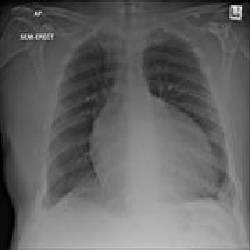

Отек легких при сердечной недостаточности является острым состоянием, при котором жидкость накапливается в тканях и альвеолах легких. Это приводит к нарушению дыхательной функции и прекращению газообмена.